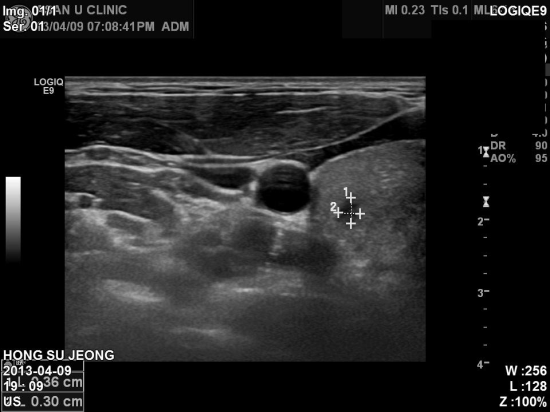

건강검진센타에서 의뢰된 0.5cm 전후의 갑상선 결절로

세포검사실시하여 갑상선 유두암 진단 받았습니다.

1cm 미만의 갑상선 결절.